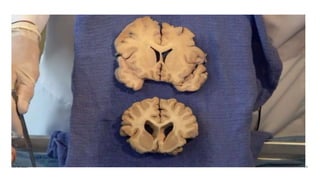

Anatomy of brain

Anatomy of ventricles